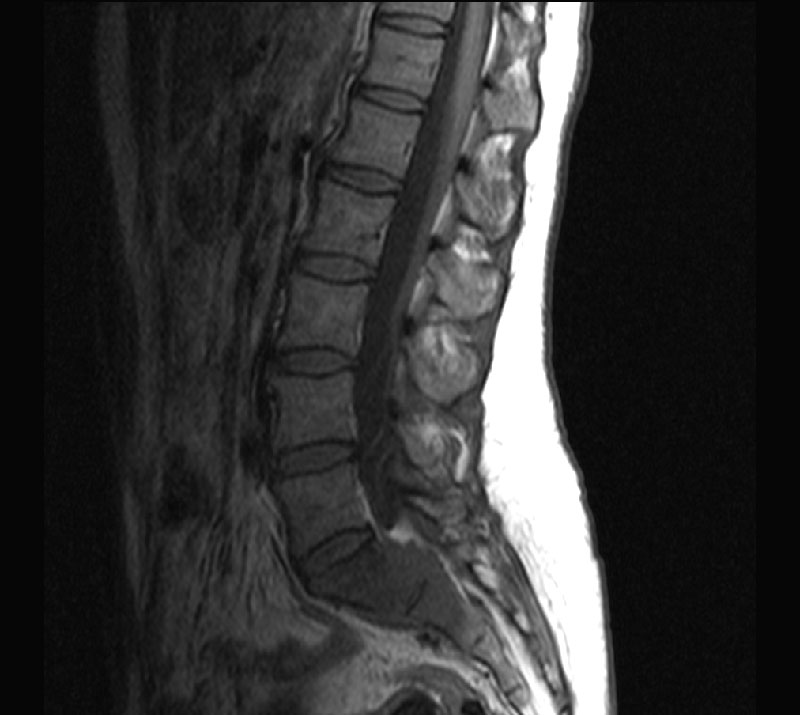

МРТ позвоночника (шейного, грудного и поясничного отделов) позволяет визуализировать структуры позвоночника (кости, нервы, мышцы, связки, диски) и подчас МРТ позволяет обнаружить патологию которую не удается диагностировать с помощью КТ, МСКТ, рентгенографии.

МРТ позвоночника позволяет обнаружить изменения, как в позвоночнике, так и в окружающих тканях (например, инфекции или опухоли).

• Обнаружить изменения в межпозвонковых дисках (протрузия или грыжа диска), наличие компрессии корешков, что является причиной радикулитов

• Выявить участки позвоночника, где есть сужение спинального канала (стеноз) и требуется оперативное лечение

Примеры исследований